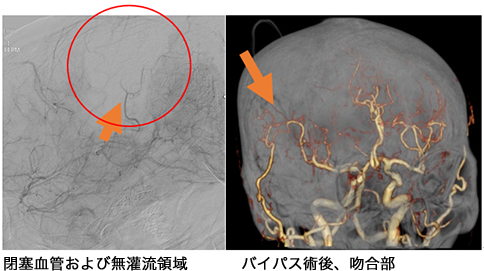

心原性脳梗塞に対する緊急バイパス術

t-PA療法が無効であったり適応外であった場合には血栓回収療法を行うわけですが、閉塞血管のすべての部位に血栓回収療法ができるわけではありません。具体的には閉塞部位が末梢(心臓から遠い)である場合には血栓回収療法は困難となります。しかし、閉塞している血管によっては運動野や言語野といった大事な血管が閉塞している場合があります。この場合には緊急で骨より外側を走っている頭皮の血管を骨の中の脳の血管につなぐバイパス手術を行います。